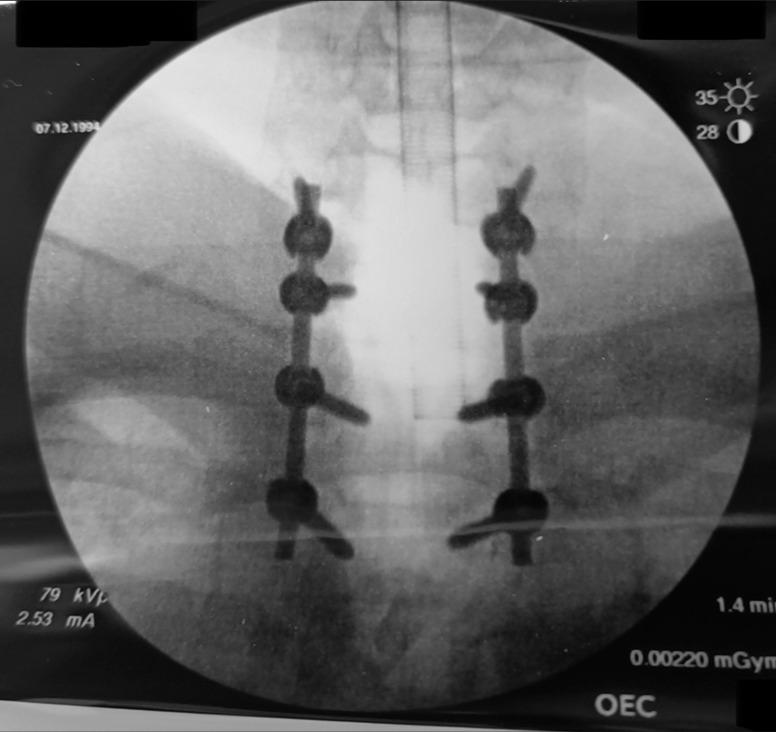

A 28-year-old male presented with a progressive quadriparesis of 12 months' duration that rapidly worsened over the last 3 months. When the MRI revealed severe cord epidural C6-T1 cord compression, the patient successfully underwent a C6-T1 laminectomy for gross total tumor excision followed by a C6-T2 instrumented fusion. The histopathology confirmed the diagnosis of a spinal JXG.

一名28岁男性,出现进行性四肢瘫12个月,在过去3个月迅速加重。MRI显示严重的硬膜外C6-T1脊髓压迫,患者成功接受了C6-T1椎板切除术以完整切除肿瘤,随后进行了C6-T2器械辅助融合术。组织病理学确诊为脊髓JXG。